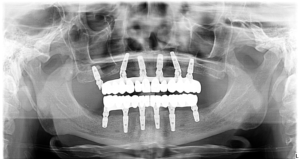

Pentru a-i reda funcționalitatea dentară, dar și o estetică armonioasă a fost nevoie de inserarea a 6 implanturi convențională la maxilar, și 6 la mandibulă.

Intervenția chirurgicală a fost realizată cu ajutorul Sedării Conștiente, pentru a-i oferi o stare de confort și pentru a nu simți durere.

Pe perioada vindecării implanturilor a fost fixată o dantură provizorie, pentru a-i permite să își continue rutina zilnica, iar la 6 luni după intervenția a fost fixată și dantura finală din zirconiu pe structură de Titan.